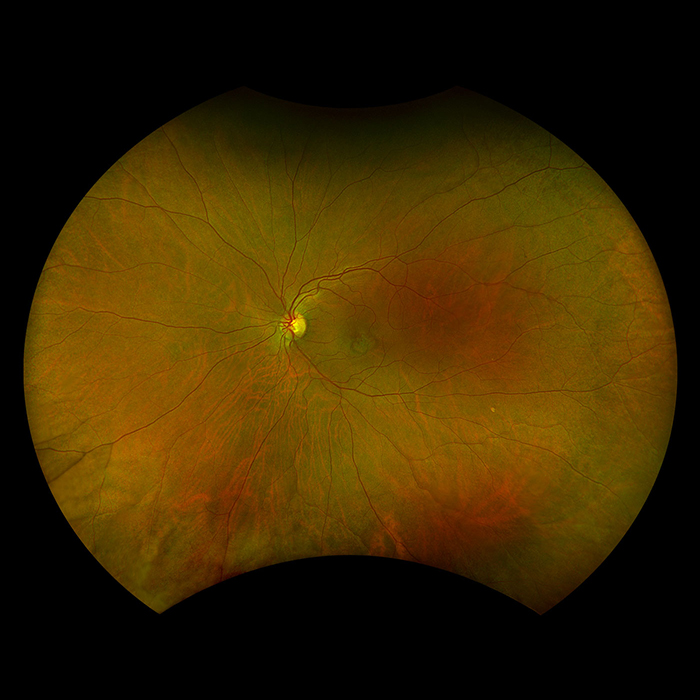

California

Unser beliebtestes Produkt, California, wurde für die medizinische Bildgebung entwickelt und ist ein Standard für Netzhautscreening-Programme. California ist in verschiedenen Bildgebungsmodalitäten erhältlich. California erzeugt in weniger als ½ Sekunde ein 200°-Bild der Netzhaut mit nur einer einzigen Aufnahme von unübertroffener Klarheit und beeinflusst das Management von Krankheiten wie DR, AMD, Geografische Atrophie, und Uveitis

Bildmodi und Ansichtsoptionen von California:

optomap Bildmodi

- Farbe rg

- Farbe rgb (verfügbar im kombinierten Modell rg/af/fa)

- Sensorisch Rotfrei

- Choroidal

- Autofluoreszenz

- Fluoreszenzangiographie

- Indocyaningrün-Angiographie